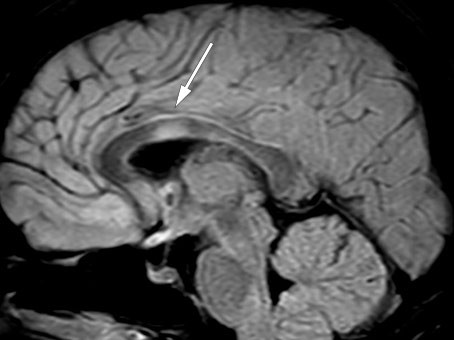

Kontroll-MR en måned senere viste tilkommet lesjon i høyre thalamus uten kontrastoppladning (figur 2) samt to nye, små lesjoner med kontrastladning i medulla ved C5, C6 og muligens også Th5. De infratentorielle lesjonene hadde gått fullstendig tilbake, og forandringene i medulla oblongata var redusert.

To måneder etter utskrivelsen fra nevrologisk avdeling ble vakthavende lege kontaktet av rehabiliteringssenteret fordi pasienten opplevde gradvis økende hodepine og kvalme samt redusert syn på venstre øye siste døgn. Vakthavende øyelege fant visus 0,05 på venstre øye og 1,2 på høyre, og mistenkte optikusnevritt. Vakthavende nevrolog fant uvuladeviasjon mot venstre og bilateralt inverterte plantarreflekser. Lumbalpunksjon viste moderat økt celletall, totalprotein og IgG (tabell 1). MR caput viste økt signal i thalamus bilateralt uten andre forandringer i hjernen og økt signal i nervus opticus bilateralt og i chiasma opticum (figur 3). Pasienten fikk igjen metylprednisolon, som hadde rask effekt.